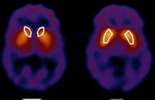

إنه فيروس الإيدز: هذا الفيروس الذي لا يزيد قطره عن واحد على عشرة آلاف من الميليمتر، سبب موت ملايين البشر في سنوات قليلة بسبب الفاحشة وما نتج عنها، فهل نعتبر نحن المسلمين، ونعتز بتعاليم ديننا الذي حمانا من هذا الوباء المهلك بعدما أعلن الغرب فشله منذ أيام في إيجاد علاج له؟........

تظهر الأبحاث العلمية يوماً بعد يوم الاختلاف بين الرجل والمرأة في كل شيء تقريباً، وفي هذه المقالة حقائق جديدة توصل إليها العلماء تأتي لتشهد على صدق هذا القرآن..........